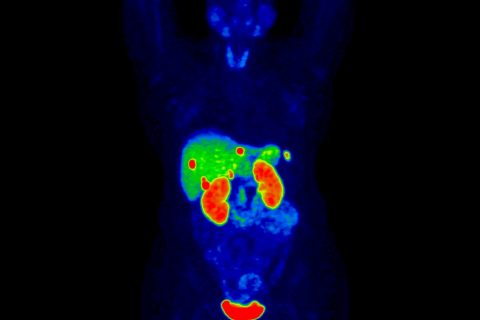

68Ga-DOTATATE

Localização de tumores neuroendócrinos (TNE) positivos para receptores de somatostatina.

68Ga-PSMA11

Para avaliação de células metastáticas de câncer de próstata.

Medicina Nuclear e Imagem Molecular em Oncologia

Desenvolvimento de radiofármacos e aplicação em modelos experimentais para estudo de doenças oncológicas, com potencial aplicação translacional em:

- Desenvolvimento de radiofármacos diagnósticos e terapêuticos

- Utilização da imagem molecular na avaliação e caracterização de processos celulares e moleculares

- Investigação do mecanismo de ação molecular do PSMA e estudo de sondas dirigidos ao PSMA em modelos tumorais.

- Desenvolvimento e estudo de nanopartículas para teranóstico

Aplicações clínicas – MN, SPECT, PET/CT e PET/RM

Investigação de métodos de medicina nuclear e imagem molecular com finalidade diagnóstica, prognóstica ou acompanhamento terapêutico de doenças oncológicas:

- PET/CT e PET/RM no estadiamento e avaliação prognóstica em oncologia

- Utilização do PET/CT no planejamento da terapia para diferentes tumores

- Técnicas de quantificação em PET/CT na avaliação prognóstica

- Utilização do PET com ligantes de PSMA no câncer de próstata e com fluoroestradiol (FES) no câncer de mama

Medicina Nuclear e Imagem Molecular em Terapia Radioisotópica

Investigação clínica da terapia radioisotópica, com destaque para aplicações oncológicas

- Ligantes de PSMA na terapia de pacientes com câncer de próstata

- Análogos de somatostatina na terapia de pacientes com carcinoma neuroendócrino